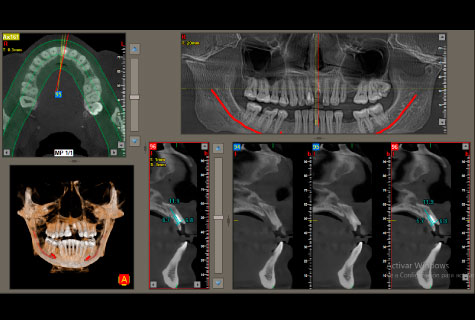

- Único que incluye programa para colocación de implantes virtual.

- Marcación del dentario inferior para un mejor diagnóstico.

Tomografía Cone Beam

- Tomografía de maxilares

- Tomografía de sector